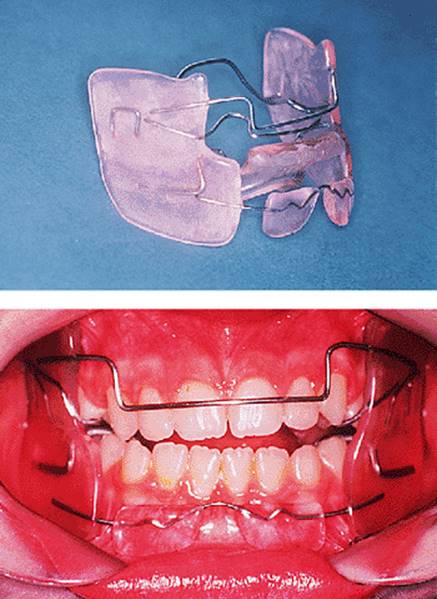

18.5.1. The Andresen activator

There are many variations upon Andresen's original design. An Andresen activator is shown in Fig. 18.5. It is a monoblock design, that is to say it comprises upper and lower acrylic appliances fused together. The original design had a solid palate, but that shown has been made with an open palate to reduce its bulk. The lower incisors are capped to minimize the tendency for them to procline during overjet reduction, and which also serves as a bite-plane to reduce the overbite. The capping resists tipping of the teeth so that any labial movement will have to be bodily translation and is therefore minimized. The labial bow lies passively against the upper incisors, and the palatal wire is again intended to minimize palatal tilting of the upper incisors.

Fig. 18.5. Andresen activator used to treat the patient shown in Fig. 18.1.

The interdental acrylic in the buccal segments has been trimmed to make a series of inclined planes which guide the eruption of the upper molars and premolars buccally and distally. The distal movement is intended to help correct the Class II buccal segment relationship. The buccal movement is needed because, as the buccal segment relationship corrects, the upper posterior teeth occlude against a wider part of the lower arch. With lower incisor eruption restricted by the capping, eruption of the molars brings about reduction of the overbite. Where the overbite is normal at the start of treatment, the molar capping should be trimmed to allow expansion but not eruption, so that the molars cannot erupt more than the incisors and cause an anterior open bite to develop (Fig. 18.6).

The appliance has no clasps; the intention is that the looseness in the mouth causes the patient to bite into it. Many patients find this difficult to tolerate in the early stages of treatment, finding that the appliance often comes out during the night, and a common modification is to clasp the upper first molars although this prevents spontaneous expansion.